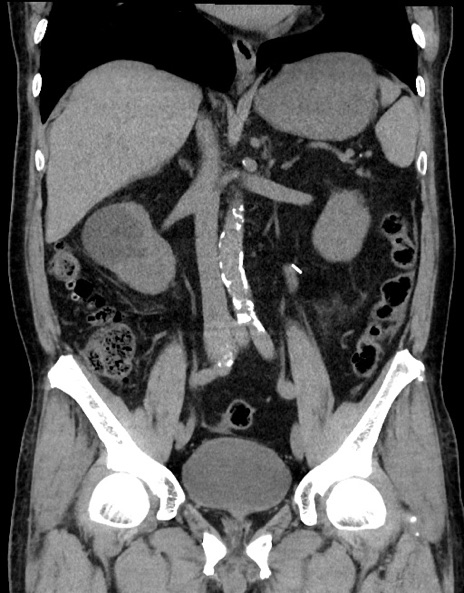

症例15(冠状断像)

【症例】70歳代男性

【主訴】腹痛

【現病歴】今朝から腹痛あり。全体的に痛い。特に左上の方。排ガスが今日はない。冷や汗が出る。

【既往歴】直腸癌術後

【身体所見】左側腹部〜上腹部に圧痛あり。腹膜刺激症状明らかなではない。軽度反跳痛。左下腹部に術後瘢痕あり。

【データ】WBC 7700、CRP 0.02